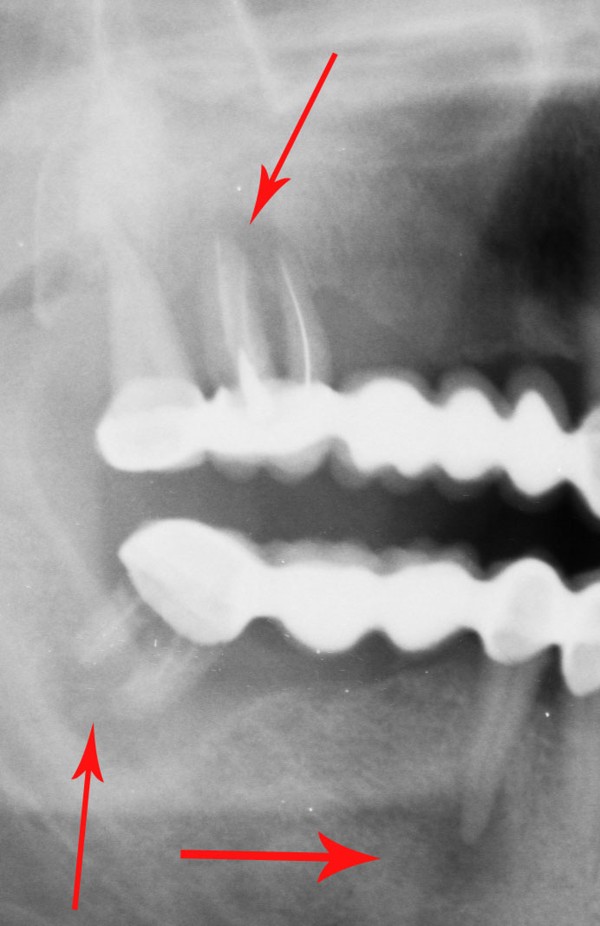

MUCHO SE HA HABLADO HASTA HOY DE LOS DISTINTOS ESQUEMAS OCLUSALES A USAR. SIN EMBARGO , HAY ALGO DE QUE ADOLECEN LAS LOS TRABAJOS PROTÉTICOS OBSERVADOS EN MÚLTIPLES LABORATORIOS DE NUESTRO MEDIO , COMO ASI DE MUCHAS PUBLICACIONES DE LOS ÚLTIMOS TIEMPOS , OLVIDANDO UN CONCEPTO TAN BÁSICO COMO EVIDENTE: PARA QUE SIRVEN LOS DIENTES. OBSERVAMOS A MENUDO GRANDES ELEVACIONES DE SENO A FIN DE LOGRAR IMPLANTAR LO IMPOSIBLE….LATERALIZACIONES DE NERVIO DENTARIO INFERIOR CON FINES SIMILARES…EXTENSAS PRÓTESIS CANTILEVER PARA REPONER LA CASI TOTALIDAD DE UNA ARCADA…Y UN SINFÍN DE RECURSOS QUE SE ACERCAN AL CRITERIO DE «ALGO HAY QUE PONER…» Y SE ALEJAN DEL SERIO SENTIDO DE «REHABILITAR». SABEMOS QUE SON MÚLTIPLES LAS FUNCIONES QUE EL SISTEMA DENTARIO CUMPLE, PERO LA FUNDAMENTAL ES MASTICAR. EN ESE SENTIDO DESDE LOS RUMIANTES, HASTA LOS CARNÍVOROS TIENEN SUS PROPIOS PATRONES A SEGUIR. EN EL CASO DEL HOMBRE, CON UNA ARTICULACIÓN TEMPOROMANDIBULAR TAN COMPLEJA Y PAUSIBLE DE DISFUNCIONES, COMO DE UN COMPLEJO MUSCULAR NECESITADO DE UNA LONGITUD ADECUADA PARA SU ORTOFUNCIÓN, LA CAPACIDAD DE MASTICAR SE VE A MENUDO ALTERADA POR LOS INNUMERABLES TRABAJOS PROTÉTICOS QUE A DIARIO SE REALIZAN EN EL MUNDO, QUE CARECEN DE LOS PATRONES NECESARIOS PARA QUE ESA FUNCIÓN SE DESARROLLE CORRECTAMENTE. LAS SUBFUNCIONES DE : INCIDIR-DESGARRAR-DISCERNIR EL ALIMENTO Y MOLER, ,PARA FINALMENTE DEGLUTIR, QUE CUMPLEN LAS DISTINTAS PIEZAS DENTARIAS , CONSTITUYEN UN CAPÍTULO DE LA ODONTOLOGÍA TAN BÁSICO Y EVIDENTE, COMO OLVIDADO . ES A MI CRITERIO FUNDAMENTAL ; PENSAR LAS DISTINTAS REHABILITACIONES ORALES POSIBLES, EN TÉRMINOS DE : EFICACIA MASTICATORIA CUANDO A MENUDO OBSERVAMOS CARAS PALATINAS DE LOS ANTERIORES CLARAMENTE CONVEXAS, O CUANDO LAS SUPERFICIES OCLUSALES DE LOS POSTERIORES SE CONSTRUYEN CON CÚSPIDES GRADO CERO, CON FINES DE MINIMIZAR LAS FUERZAS EXPULSIVAS DE UNA PRÓTESIS O LAS FUERZAS TANGENCIALES A LOS IMPLANTES, …LA EFICACIA MASTICATORIA, DISMINUYE SENSIBLEMENTE , CUANDO NO SE PROVOCAN DISFUNCIONES IATROGÉNICAS A VECES MAS DIFÍCILES DE RESOLVER QUE EL ESTADO INICIAL DE LA BOCA. DE LA MISMA MANERA, LA CONSERVACIÓN PROLONGADA DE PIEZAS EN ESTADO TERMINAL, MUCHAS VECES PROVOCA LA PÉRDIDA EXAGERADA DE HUESO ALVEOLAR, MANTENIENDO LOS MISMOS CON SUPRAESTRUCTURAS QUE AGRAVAN LA SITUACIÓN. SI BIEN ES CIERTO, QUE LA CONSERVACIÓN DE PIEZAS DENTARIAS , MUCHAS VECES EN «ESTADO CAÓTICO», NOS SIRVEN PARA SOPORTAR ELEMENTOS PROVISIONALES DE ALTA EFICACIA DURANTE EL TRATAMIENTO REHABILITADOR….Y QUE LAS MISMAS ADQUIEREN ESTADOS MUCHO MAS BENÉFICOS DURANTE SU PROVISORIA FUNCIÓN, TAMBIÉN ES CIERTO, QUE CON VISTAS A UNA MAYOR «EFICACIA MASTICATORIA», LA CONSERVACIÓN DEL HUESO RESIDUAL POST EXTRACCIÓN, ADECUADAMENTE TRATADO , SUELE SER DE MAS UTILIDAD , QUE LA CONSERVACIÓN PROLONGADA DE ELEMENTOS DENTARIOS ALTAMENTE DESTRUIDOS. SALZMAN, EN 1.947 COMPROBÓ QUE PUEDE NO EXISTIR EL MOVIMIENTO HORIZONTAL MANDIBULAR DURANTE LA MASTICACIÓN DE ALIMENTOS BLANDOS, MIENTRAS QUE LOS ALIMENTOS DUROS QUE NECESITAN MAS PRESIÓN, DAN FORZOZAMENTE LUGAR A LA TRANSTRUSIÓN. JANKELSON, HOFFMAN Y HENDRON, EN 1.953, ESTABLECIERON QUE LA MASTICACIÓN, BILATERAL ALTERNADA, ERA NECESARIA PARA LA MANUTENCIÓN DE LAS ESTRUCTURAS DE SOPORTE, Y QUE LAS MASTICACIONES UNILATERALES O PROTRUSIVAS ERAN PRODUCTO DE INTERFERENCIAS OCLUSALES. CIERTOS ESTUDIOS REALIZADOS CON CINEFLUOROSCOPÍA HAN DEMOSTRADO QUE NO EXISTE NINGÚN CONTACTO DENTARIO DURANTE LA MASTICACIÓN . NO OBSTANTE ADAMS Y ZANDER EN 1.964, CON MÉTODOS DE BASADOS EN LA MULTIPLICIDAD DE ESTUDIOS PRODUCIDOS ACERCA DE LA FISIOLOGÍA DE LA MASTICACIÓN , ES IMPENSABLE HOY, A LA ALTURA DE LOS CONOCIMIENTOS ACTUALES , ESCAPAR A LA NORMA INELUDIBLE DE FORMA = FUNCIÓN POR ELLO ES NECESARIO , ANALIZAR LAS REHABILITACIONES EN FORMA GLOBAL E INTESIVAMENTE , YA QUE , POR EJEMPLO , LA SIMPLE INSTALACIÓN DE IMPLANTES DENTALES , POR MUY INTEGRADOS QUE ESTEN , DE NADA SIRVEN SI NO EXISTE UNA CONGRUENCIA ENTRE LAS FORMAS QUE CUMPLAN LAS FUNCIONES ESPECÍFICAS PARA LAS CUALES HA SIDO CREADO EL SISTEMA. EN LAS SIGUIENTES FOTOGRAFÍAS PERTENECIENTES A UN MISMO CASO , SE OBSERVA CLARAMENTE QUE SI BIEN SE HAN COLOCADO LAS PIEZAS FALTANTES EN UN ÁREA EDÉNTULA , DE POCO SERVIRÁN YA QUE LA GUIA CANINA DEL LADO OPUESTO ES INEXISTENTE, ADEMÁS DE QUE LAS SUPERFICIES OCLUSALES DIFÍCILMENTE CUMPLAN CON LA EFICACIA MASTICATORIA. EN LA MASTICACIÓN OMNÍVORA LOS CONTACTOS OCLUSALES SON INEXISTENTES SALVO EN LA ÚLTIMA FASE DEL CICLO MASTICATORIO. EL CICLO MASTICATORIO CONSTA DE DISTINTAS FASES DE LAS CUALES LA INICIAL , CONSISTE EN LA: POSTERIORMENTE , LA MANDIBULA EJERCE UN MOVIMIENTO LATERAL HACIA EL LADO (LADO DE TRABAJO) DONDE SE HA UBICADO EL ALIMENTO : A CONTINUACIÓN LA MANDIBULA LATERALIZADA COMIENZA EL CIERRE , HASTA CONTACTAR LOS CANINOS ENTRE SI : DONDE EL SUPERIOR SEÑALA EL CAMINO A SEGUIR DEL CANINO INFERIOR (QUE ES SOLIDARIO A LA MANDIBULA TODA), DESDE EL PUNTO DEL PRIMER CONTACTO (BORDE A BORDE CANINO , O SUS CERCANÍAS ), HASTA AQUEL PUNTO TERMINAL ,DEL RECORRIDO CANINO QUE SEÑALA LA: …….. DEL RESTO DE LAS PIEZAS. DURANTE ESA APROXIMACIÓN HACIA LA MÁXIMA INTERCUSPIDACIÓN ( LO QUE ES LO MISMO QUE HACIA LA RELACIÓN CÉNTRICA EN UNA OCLUSIÓN ORGÁNICA..) , LOS REBORDES MARGINALES MESIALES Y DISTALES , JUNTO A LAS TRIANGULARES INTERNAS DE LAS PIEZAS POSTERIORES DESBRIDAN EL ALIMENTO EN CICLOS CADA VEZ MAS PEQUEÑOS, A MEDIDA QUE EL ALIMENTO SE DESTRUYE. LAS PIEZAS DENTARIAS SE VAN APROXIMANDO ENTRE SI CADA VEZ MAS , INTERDIGITANDO SUS CÚSPIDES , SEGÚN EL MECANISMO ANTERIOR , HASTA ALCANZAR UN BOLO ADECUADO PARA DEGLUTIR. DE LA MISMA MANERA QUE LO HACE UNA TIJERA. ASI, ES COMO ACTUAN LAS CÚSPIDES DENTARIAS ¿CUAL SERÁ ENTONCES EL EFECTO DE UNA MASTICACIÓN CARENTE ABSOLUTAMENTE DE ANATOMÍA? FRENTE A UNA MASTICACIÓN QUE OPERE SEGÚN: FORMA = FUNCIÓN ¿? ES EVIDENTE QUE LA INEFICACIA PRODUCTO DE LA FALTA DE ANATOMÍA ADECUADA REDUNDARÁ EN UN MAYOR ESFUERZO MASTICATORIO , Y SERÁ EL RESTO DEL APARATO DIGESTIVO QUIEN SE ENCARGUE DE LAS DESTRUCCIÓN DE LOS ALIMENTOS PARA QUE ESTOS SEAN DIGERIDOS. REHABILITAR LAS SUPERFICIES OCLUSALES , COMO ASI REPONERLAS CON UN CRITERIO ANATÓMICO FUNCIONAL , DONDE LA ALTURA CUSPÍDEA , LA GUÍA CANINA, LA CREACIÓN DE ESPACIOS UNIFORMES DURANTE EL FENÓMENO DE LUCE , LA DISCLUSIÓN ABSOLUTA DE TODAS LAS UNIDADES DE OCLUSIÓN DURANTE UNA TRANSTRUSIÓN , TANTO DEL LADO ACTIVO COMO DEL NO ACTIVO, EN ARMÓNICA CONGRUENCIA CON LA LONGITUD MUSCULAR Y EL FISIOLOGISMO ARTICULAR , CONSTITUYEN LAS BASES PARA CONSTRUIR REHABILITACIONES QUE REPONGAN Y MANTENGAN LA EFICACIA MASTICATORIA.

FIG 12